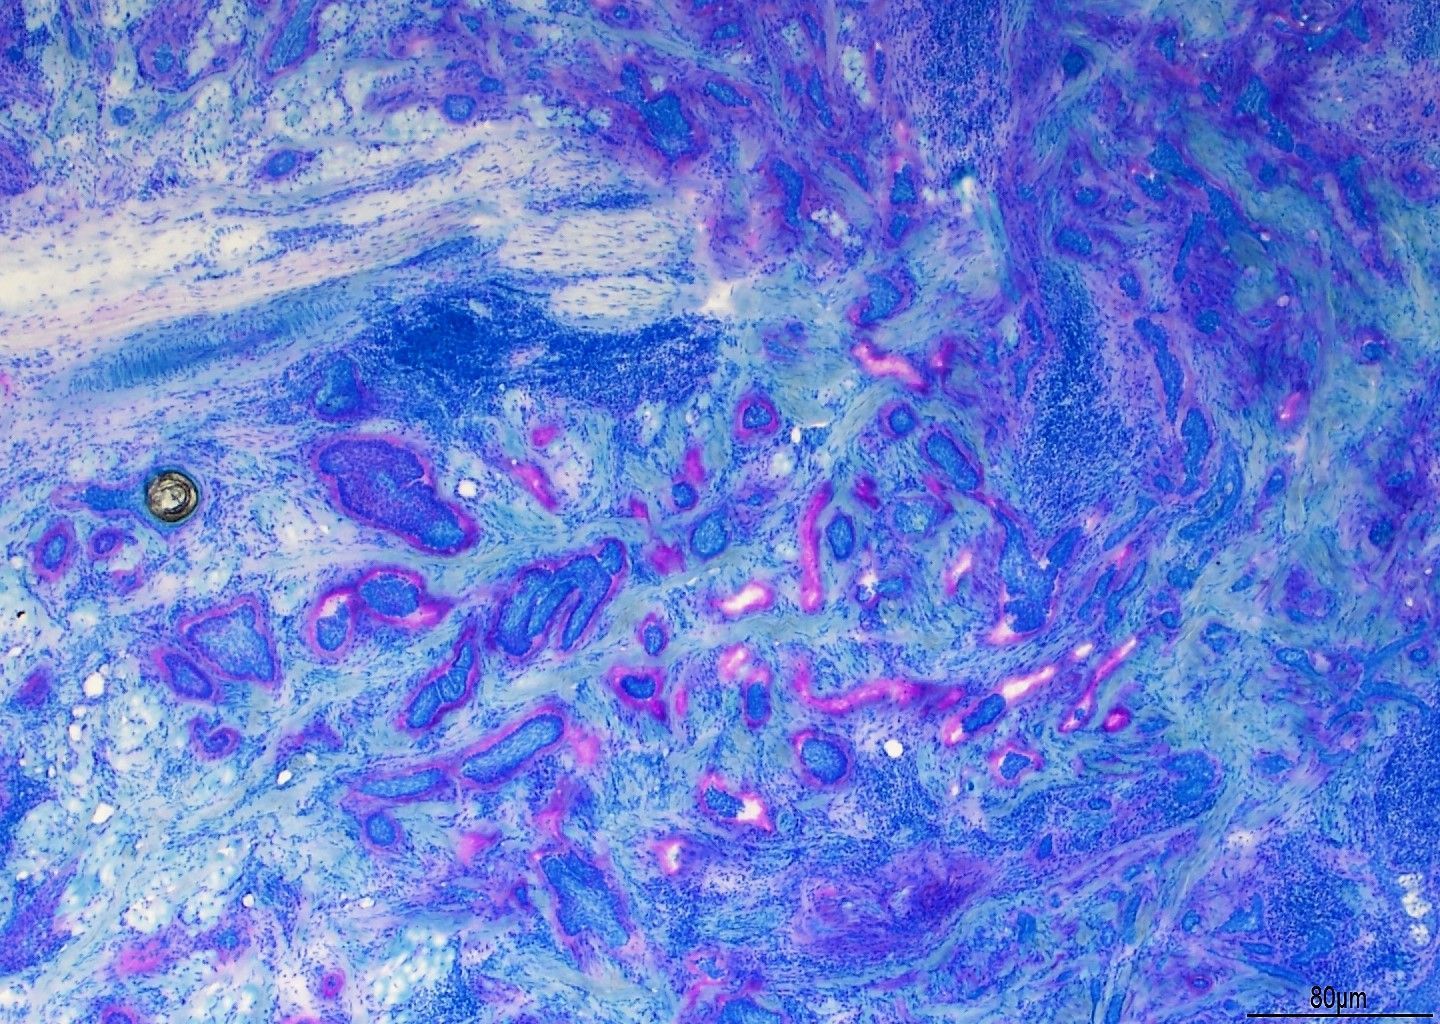

- Demonstracija specifičnih ciljeva krvnih stanica unutar biopsije BMT-a

- Dijagnostički polutanki rezovi smole